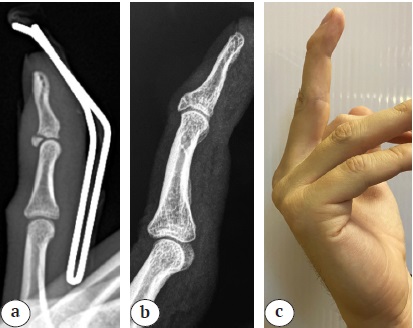

Наибольшее влияние на остаточный дефицит разгибания оказали тип повреждения по J.R. Doyle и выбранный способ лечения. При повреждениях IVB и IVC типах остаточная деформация составила 20° [12–25 и 20–30 соответственно], в то время как при I типе 15° [4–20] (p<0,001, критерий Краскела – Уоллиса). В основном причиной более выраженного дефицита при повреждениях IVB и IVC типов являлось сращение перелома со смещением отломков, результатом которого была «клювовидная» деформация ногтевой фаланги (рис. 2).

Рис. 2. Повреждение mallet finger IVB типа по J.R. Doyle:

a — рентгенограмма после иммобилизации шиной;

b — рентгенограмма спустя 2 года после консервативного лечения: клювовидная деформация ногтевой фаланги и признаки деформирующего артроза ДМФС 2-й стадии;

c — внешний вид пальца спустя 2 года после лечения

Figure 2. Type IV mallet finger injury according to the Doyle classification:

a — X-ray after immobilization with a splint;

b — X-ray 2 years after conservative treatment showing a deformity of the nail phalanx and signs of deforming osteoarthritis in the DIP joint, stage 2;

c — appearance of the finger 2 years after treatment